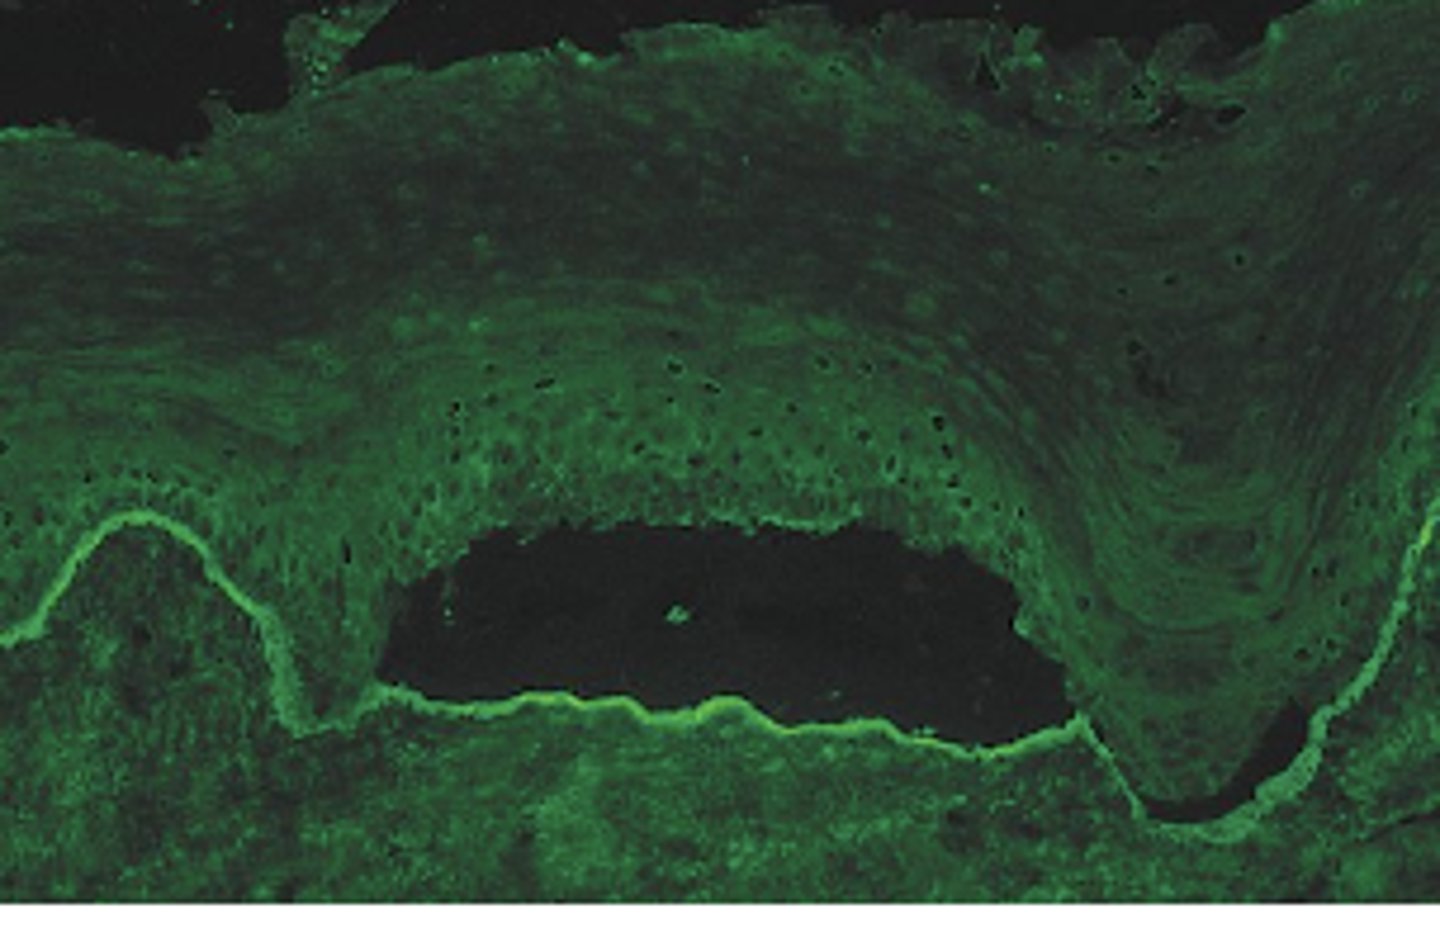

Blistering in this disease is due to antibodies directed against component of ___? (picture showing histo slide with intraepithelial split)

What cell layer is affected in pemphgUs (PICTURE ON DRIVE)?

Blistering in this disease is due to antibodies directed against component of ___? (picture showing histo slide with basement layer split)